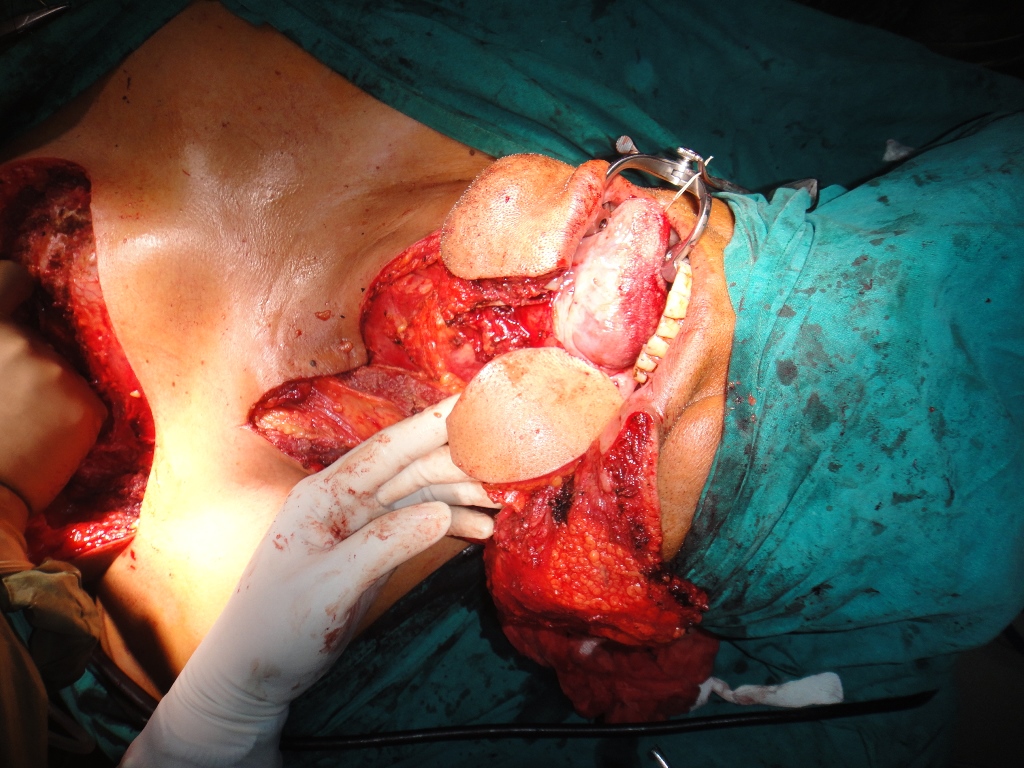

52 yrs old male suffering from right lower gingivo buccal carcinoma. Operated today for right radical neck dissection with right PM flap with right heminmandibulectomy.